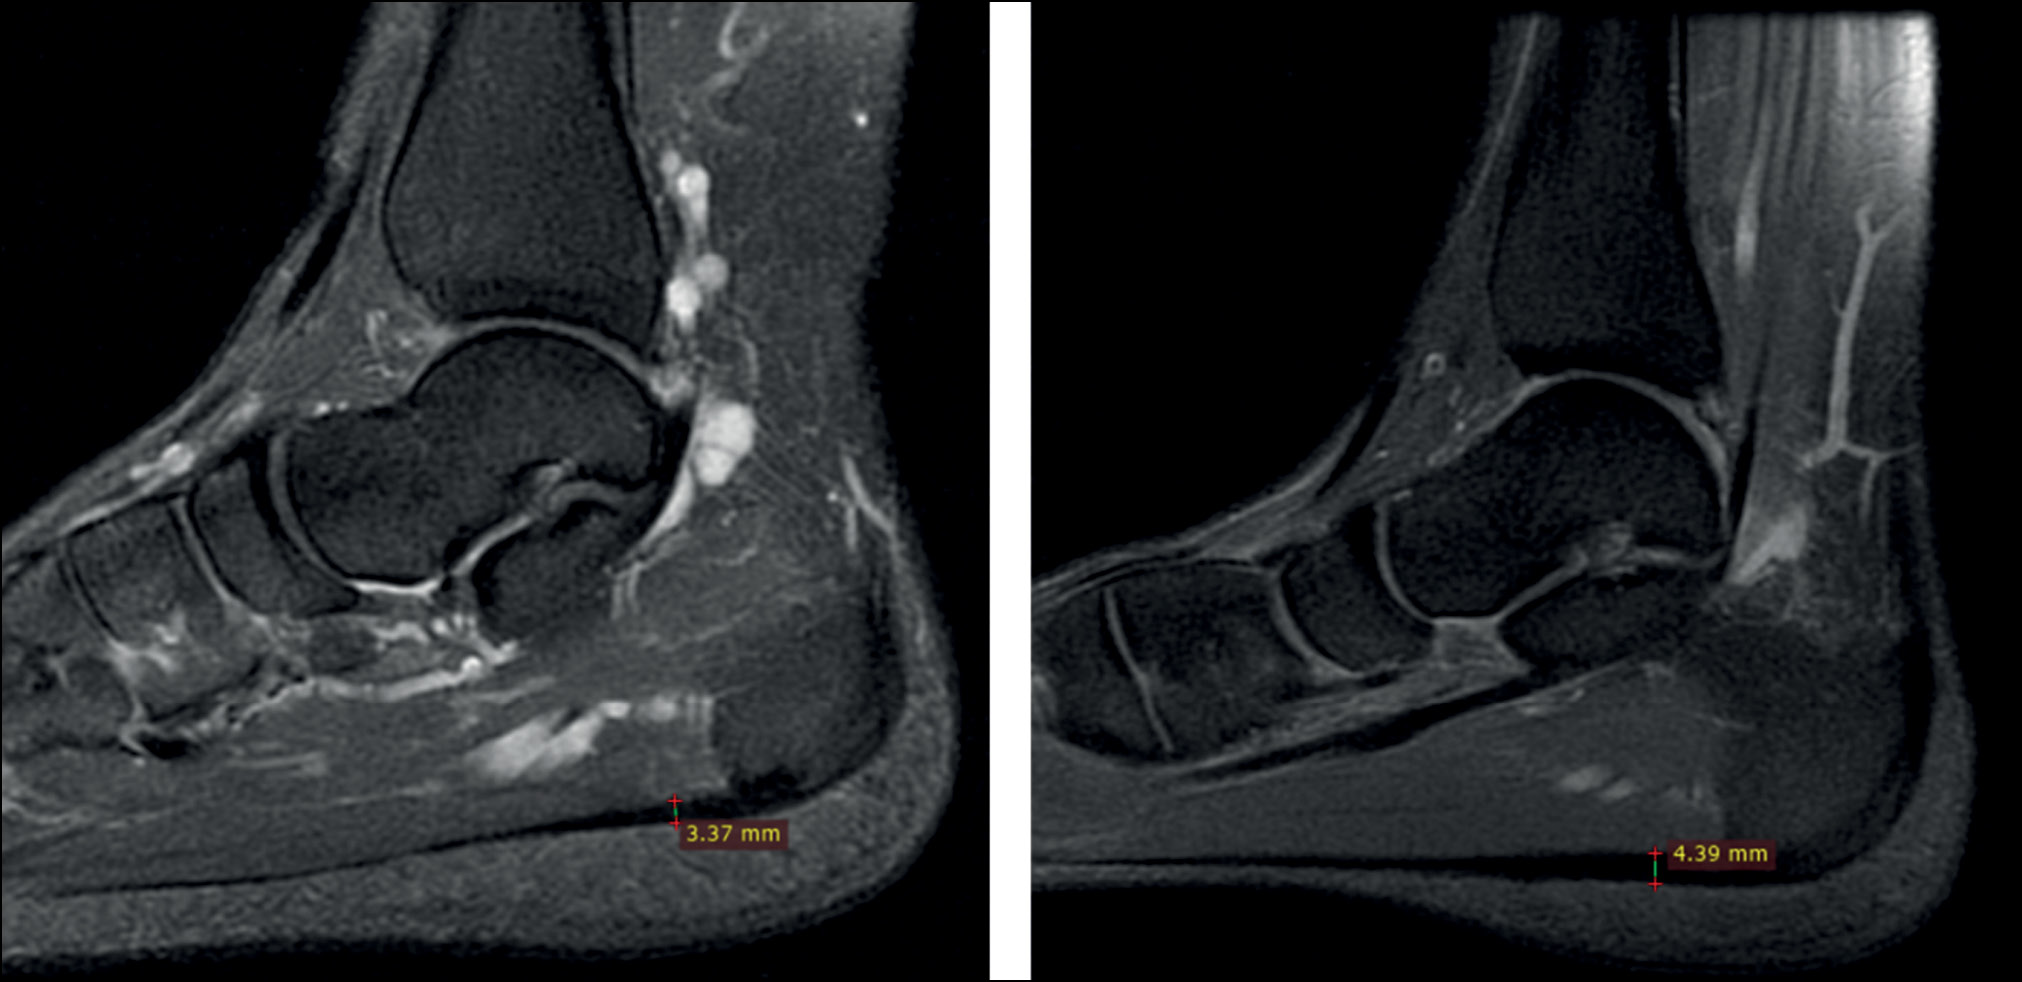

В текущем исследовании мы определяли толщину плантарной фасции только у спортсменов с ПФ. Толщина определялась на сагиттальных срезах Т2-взвешенных изображений стопы и голеностопного сустава, отступив 1 см от края пяточной кости (рис. 7).

Рис. 7. Сагиттальные срезы Т2-взвешенных изображений стоп спортсменов с плантарным фасциитом.

Fig. 7. Sagittal slices of T2-weighted images of the feet of athletes with plantar fasciitis.

Медиана толщины плантарной фасции у спортсменов с ПФ составила 4,08 (3,47; 4,74) мм.